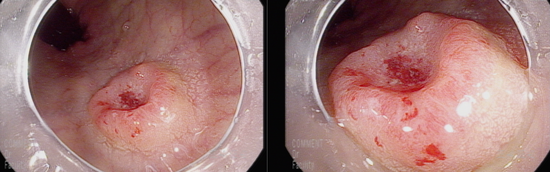

항문연 7cm상방에 중앙에 함몰을 보이는 12mm 크기의 종괴, 직장암으로 조직검사 시행

U턴을 하지 않으면 내시경 후퇴시 지나칠 수 있는 위치임.

U턴을 하지 않더라도 좁은 곳이므로 내시경을 돌려가며 관찰하면 놓치지 않고 관찰할 수 있음.

조직결과; Consistent with Adenocarcinoma, well differentiated